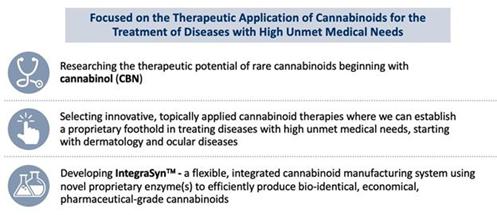

We are a clinical stage pharmaceutical company developing a pipeline of prescription-based products targeting treatments for diseases with high unmet medical needs as well as developing proprietary manufacturing technologies.

We are developing an integrated biosynthesis-based manufacturing approach, called IntegraSynTM, for synthesizing pharmaceutical-grade cannabinoids, for potential use in product candidates. We are dedicated to delivering new therapeutic alternatives to patients who may benefit from cannabinoid-based medicines. Our approach leverages on the several thousand years’ history of health benefits attributed to the Cannabis plant and brings this anecdotal information into the 21st century by applying tried, tested and true pharmaceutical drug development discipline and a scientific approach to establish non-plant-derived (synthetically manufactured), individual cannabinoid compounds as clinically proven, FDA-approved medicines. While our activities do not involve direct use of Cannabis nor extracts from the plant, we note that the U.S. Food and Drug Administration (“FDA”) has, to date, not approved any marketing application for Cannabis for the treatment of any disease or condition and has approved only one Cannabis-derived and three Cannabis-related drug products. Our APIs, which are the ingredients that give medicines their effects, are synthetically made and, therefore, we have no interaction with the Cannabis plant. We do not grow nor utilize Cannabis nor its extracts in any of our products; our products are applied topically (not inhaled nor ingested); and, we do not utilize THC or CBD, the most common cannabinoid compounds that are typically extracted from the Cannabis plant, in any of our products. The API under development for our initial two drug candidates, INM-755 for EB and INM-088 for glaucoma, is CBN. Additional uses of both INM-755 and INM-088 are being explored, as well as the application of additional rare cannabinoids to treat diseases.

We believe we are positioned to develop multiple product candidates in diseases which may benefit from medicines based on rare cannabinoid compounds. Most currently approved cannabinoid therapies are based specifically on CBD and/or THC and are often delivered orally, which has limitations and drawbacks, such as side effects (including the psychoactive effects of THC). Currently, we intend to deliver our rare cannabinoid pharmaceuticals through various topical formulations (cream for dermatology, eye drops for ocular diseases) as a way of enabling treatment of the specific disease at the site of disease while seeking to minimize systemic exposure and any related unwanted systemic side effects, including any drug-drug interactions and any metabolism of the active pharmaceutical ingredient by the liver. THC and CBD can be obtained either from plant extraction or chemically synthesized. We plan to access rare cannabinoids via all non-extraction approaches, including our IntegraSynTM approach, thus negating any interaction with or exposure to the Cannabis plant.

Our Strengths

We are the only clinical-stage company with both multiple cannabinoid drug candidates, in multiple therapeutic categories, that also is developing an integrated biosynthesis-based manufacturing approach, called IntegraSynTM, to meet the needs of the rapidly evolving pharmaceutical drug needs for rare cannabinoids. Key strengths include:

Innovative IntegraSynTM manufacturing approach.

IntegraSynTM is our integrated cannabinoid synthesis approach designed to efficiently produce bio-identical, economical, pharmaceutical-grade cannabinoids. IntegraSyn’sTM scalable and flexible manufacturing approach integrates multiple commercially proven methods to efficiently produce cannabinoids utilizing cost-effective processes.

Targeting medical applications of rare cannabinoids to treat diseases with high unmet medical needs.

Significant investment in understanding the therapeutic potential of CBN has provided us with important insight as to how best to develop this class of compounds for treating various diseases. We intend to apply this know-how across several diseases that may benefit from cannabinoid-based medicines.

Our Business Strategy

Our goal is to become a global leader in the manufacturing and clinical development of rare cannabinoids while continuing to avoid any direct interaction with the Cannabis plant. Our strategies to accomplish this include:

Develop a cost-efficient manufacturing source for high quality rare cannabinoids as API for our core internal drug candidate pipeline, for licensing opportunities of non-core drug candidates, as well as a potential source for cannabinoids in the non-pharmaceutical space.

Extraction of rare cannabinoids from the plant is economically impractical for commercial applications. Modern approaches to product manufacturing, including chemical synthesis and biosynthesis, may be appropriate in individual situations depending on the targeted cannabinoid, the quantity that is desired as well as the requisite quality specification for the intended market segment (consumer vs. pharmaceuticals). We are developing an integrative cannabinoid synthesis approach designed to produce bio-identical, economical, pharmaceutical-grade cannabinoids in a cost-efficient manner, called IntegraSynTM, that may bring incremental benefits over the traditional chemical synthesis and biosynthesis approaches. The cannabinoids that will be produced from IntegraSynTM are targeted to be bio-identical to the naturally occurring cannabinoids. Our manufacturing approach is designed to offer superior yield, control, consistency and quality of rare cannabinoids when compared to alternative methods. IntegraSynTM may address the increasing pharmaceutical and other commercial demands for competitively-price cannabinoids while providing access to rare cannabinoids that are otherwise impractical to extract from the plant.

We have numerous options for commercializing our various technologies. At the core of our activities, we are a drug development company focused on commercializing important cannabinoid-based medicines to treat diseases with high unmet medical needs.